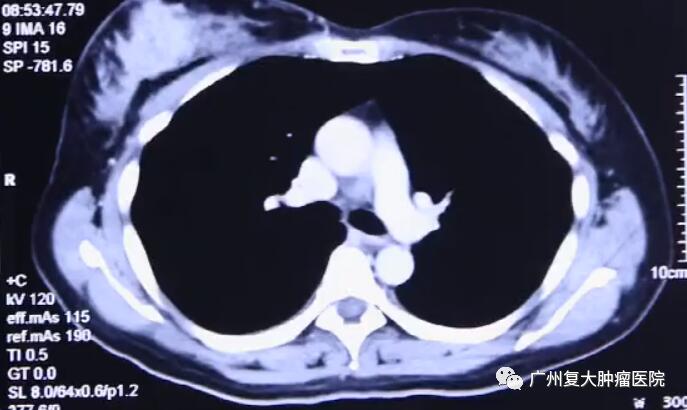

影像结果显示

超声引导下将探针插入肿瘤区内,当温度下降超过一定水平时,冰晶开始在肿瘤细胞内部形成,冻结供应营养的血管,停止运输养分,摧毁肿瘤细胞组织。持续几分钟后,迅速又复温。经过这样两个循环后,肿瘤病灶完全被“冻结”,进而达到治疗效果。由于病灶位置浅,离皮肤较近,因此在术中还要对皮肤采取保护措施,以免冻伤皮肤。

3天后Mary就恢复日常活动能力,术后半年她体内的肿瘤指标已下降到正常范围了。10年来,Mary的健康情况良好,复查显示肿瘤现在仅剩一个疤痕。